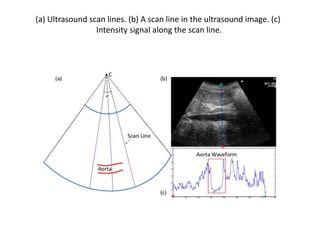

(a) Ultrasound scan lines. (b) A scan line in the ultrasound image. (c)

Intensity signal along the scan line.

• Scan line &line density • Scan line allows the ultrasound transducer to see from multiple lines of site at different angles, as opposed to the standard line-of-site that's perpendicular to the transducer lens. Slide (20) • Line density in a sector image is the number of scan lines per • degree of sector. • Line density in a rectangular image is the number of scan lines per centimeter. • When the line density is low, temporal resolution is high. •